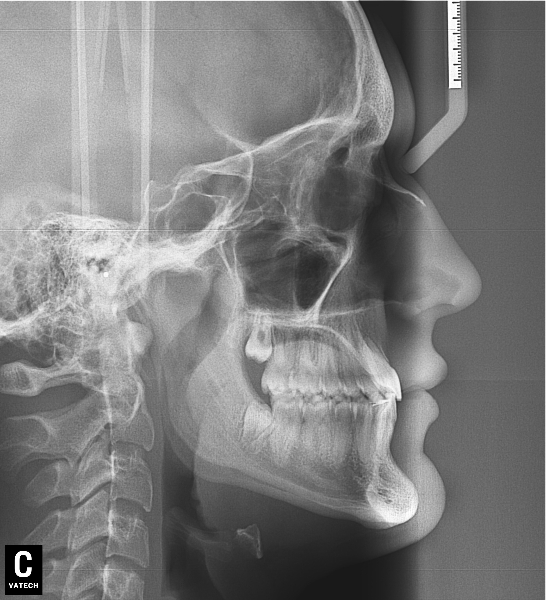

El paciente E.A. acude a nuestra consulta por diastema inferior y ausencia de contactos en los sectores laterales.

Chica de 17 años tratada en 1 año con stripping en los dientes inferiores